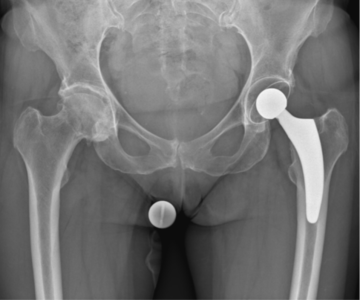

In der Hüftendoprothetik verwenden wir knochensparende zementfreie Kurschaftprothesen sowie zementfreie und zementierte Geradschaftprothesen. Die Gelenkpfannen, bestehend aus Titan mit einem Polyethyleninlay, werden in Regel zementfrei im Becken verankert. Nach Anfertigung spezieller Röntgenaufnahmen vor der Operation erfolgt eine genaue digitale Planung der Prothese, individuell auf die Anatomie des Patienten abgestimmt.

Die Gleitpaarung wird gebildet aus hochvernetztem, mit Vitamin E versetztem Polyethylen (XLPE oder Vitamin E-XLPE) in der Gelenkpfanne, zusammen mit dem neuen Hüftkopf aus sehr harter Keramik. Optimale Materialkombination mit sehr wenig Abrieb in Kombination mit großer Erfahrung in der minimalinvasiven Implantationstechnik sind die Voraussetzung für eine lange Funktionsdauer des neuen Gelenkes.

Hüftprothese nach OP

(Optimys Kurzschaft)